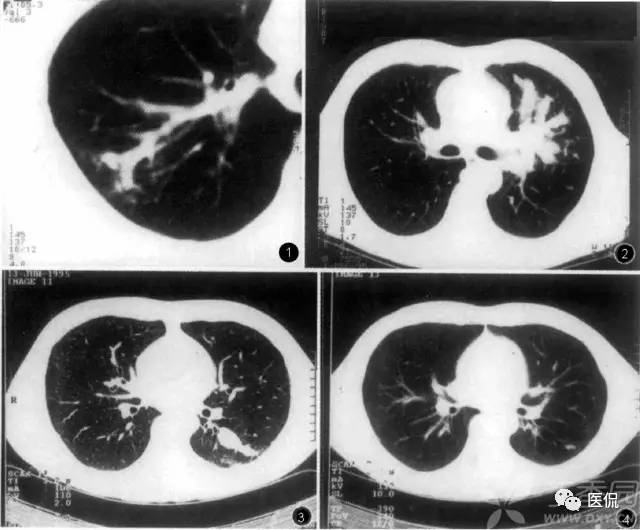

树芽征

是指病变累及细支气管时,由于炎性渗出物或分泌物堵塞细支气管,CT表现为小叶中心分枝状线影和与其相连的细支气管横断面结节影,状如春天里挂满枝芽的“树”,即“树芽征”。是细支气管扩张、阻塞的特征影像之一。肺小叶是构成肺的最小结构单位,直径约10 25mm,小叶之间为结缔策划间隔,每个肺小叶都有一支小叶支气管(直径≤lmm)和小叶肺动脉进入,二者皆位于小叶的中心。CT不能显示直径小于2mm支气管,故正常小叶支气管CI’扫描时不显示,但当小叶支气管发生病变时,CT就可以显示出来。

树芽征的小叶中心结节影和分枝状线影是同一病理结果的不同影像表现,二者的病理基础都是细支气管的扩张与阻塞,CT横断面像呈平行走向的细支气管表现为分枝状线影,呈垂直或斜向走行者表现为结节影。原发或继发于细支气管的病变(如炎症)可导致细支气管壁增厚、细支气管扩张,当同时伴有分泌物潴留时,支气管“树”状如春天里一棵挂满枝芽的“树”。随着气道的继续扩张和肺实质病变的出现,支气管“树”会进一步扩展。当大气道扩张伴有周围小气道气体潴留时,就类似于支气管疾病时大气道堵塞所形成的“指套征”。

树芽征的相关疾病有:肺支气管的感染性病变,免疫性疾病如变应性支气管肺型曲霉菌病,先天性疾病如囊性肺纤维化及纤毛运动异常综合征(Dyskinetic’s综合征),肿瘤性疾病如少年型喉气管支气管乳头状瘤病,吸人刺激性物质,弥漫性全支气管炎及阻塞性细支气管炎,血管性疾病等等。